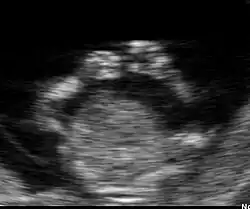

Embryon à 8 semaines

L'embryon mesure entre 15 et 22 mm. La vésicule vitelline qui le nourrit est juste à côté. À la fin de cette semaine, les coudes deviennent visibles